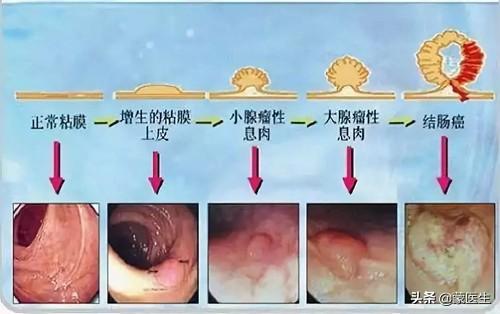

腸の腺腫様ポリープ → 腸がん

腸ポリープは、腺腫性ポリープ、炎症性ポリープ、過形成性ポリープに分類される。腺腫性ポリープは5~15年でがんになる可能性がある。炎症性ポリープと過形成性ポリープは、現在のところ癌化する可能性は低いと考えられているが、大腸内視鏡下ではポリープの性状を形態学的に判断することができないため、一般的には大腸内視鏡下で切除し、病理標本にすることが推奨されている。最終的な判定が腺腫性ポリープであったとしても、また嵐の中で "リーキーフィッシュ "を起こさないように、毎年検査を受ける必要がある。

腸ポリープ

最も有望なミニオンは以下の通り。結腸・直腸ポリープ癌にエスカレートする可能性が最も高く、多くの場合、複数の分布があり、通常は隠れた増殖で、「変形」が結腸癌になることもある。

腸ポリープは表面が非常にもろく、また出血しやすい。 患者は血便に気づいたら受診するが、患者の状態ももはや深刻ではないことが多い。

腸ポリープには大きく分けて炎症性と腺腫性の2種類があり、前者はほとんどが悪性ではなく、後者は悪性の可能性が高い。

統計上、大腸がんの80~95%は腸ポリープから段階的に進行し、その過程には5~10年かかる!

ポリープから癌への進行性進展

5.腸管ポリープ:家族性多発性腸管ポリープ症は染色体優性疾患であり、一つの遺伝子が多面的に発現する。大腸ポリープは腺腫性ポリープであり、発癌率は50%である。病気の経過の延長、加齢、免疫力の低下により発癌率はさらに高くなり、家族歴があれば男女ともに罹患する可能性がある。家族歴があると男女ともに大腸腺腫性ポリープが発生し、次の世代の年齢が進み、20歳前に大腸腺腫性ポリープがんが発生することさえある。また、一般的な腸管ポリープでも発癌のリスクはあり、腸管腫瘍の大部分は腸管腺腫から緩徐に発生する。 ポリープが大きいほど発癌率は高く、ポリープの数が多いほど発癌率は高く、ポリープの病理学的タイプでは腺腫性絨毛成分が多いほど発癌率は高く、先端部のある腺腫性ポリープは発癌率が低く、基部の広い腺腫性ポリープは発癌率が高く、直腸ポリープは発癌率が高い。

- 腸癌の前癌病変としての大腸多発性腺腫性ポリープ.大腸で増殖するため発見が容易ではなく、血便、粘液便、腸重積を呈することがあり、主に大腸内視鏡検査で発見される。定期的なフォローアップ大腸内視鏡検査で腸癌への進行を防ぐ。